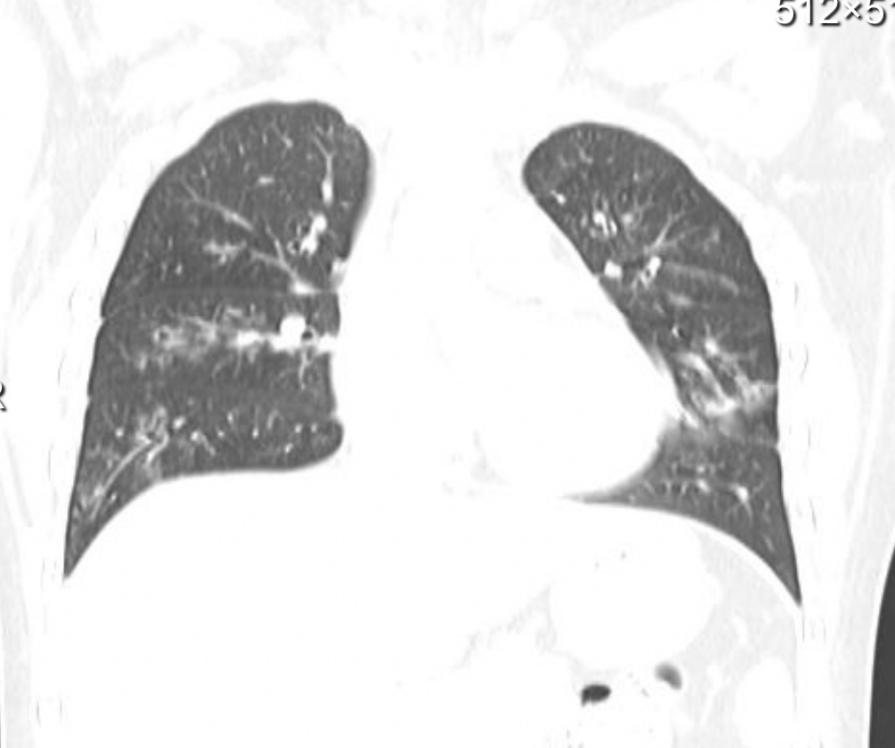

一是磨玻璃影,这是早期甲流肺炎的典型表现之一。在CT影像上,肺部会出现类似“薄雾笼罩”的半透明阴影,提示肺泡内有少量炎性渗出物。这种病变多位于肺部外周区域,早期可能范围较小,若未及时干预会快速扩散。二是斑片状或大片状实变影,随着病情进展,炎性渗出物增多,肺泡被填充,影像上会出现密度增高的片状阴影,严重时可累及多个肺叶。三是肺部纹理异常,轻症感染者可能仅表现为肺部纹理增粗、模糊,提示支气管黏膜存在炎症反应。少数重症患者还可能出现胸腔积液、肺不张等并发症,在影像上可观察到胸腔内液体增多、肺部组织塌陷等表现。

Ct冠状重组示例